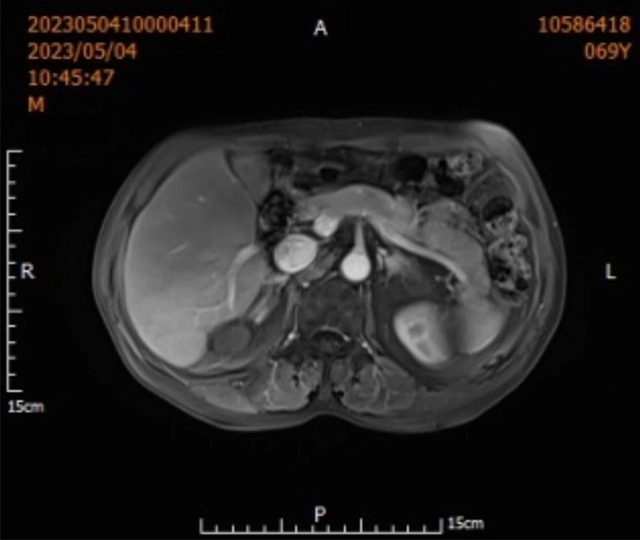

术后三天吴大叔就康复出院,定期于肝胆病科门诊复诊,病情一直很稳定。

定期复查非常重要,早发现,早治疗,术后1月左右复查肝脏肿瘤标志物、肝脏增强核磁共振或CT、肝功能等。

病情稳定后通常情况下每隔2~3月复查肿瘤标志物、彩超、增强MRI或CT。